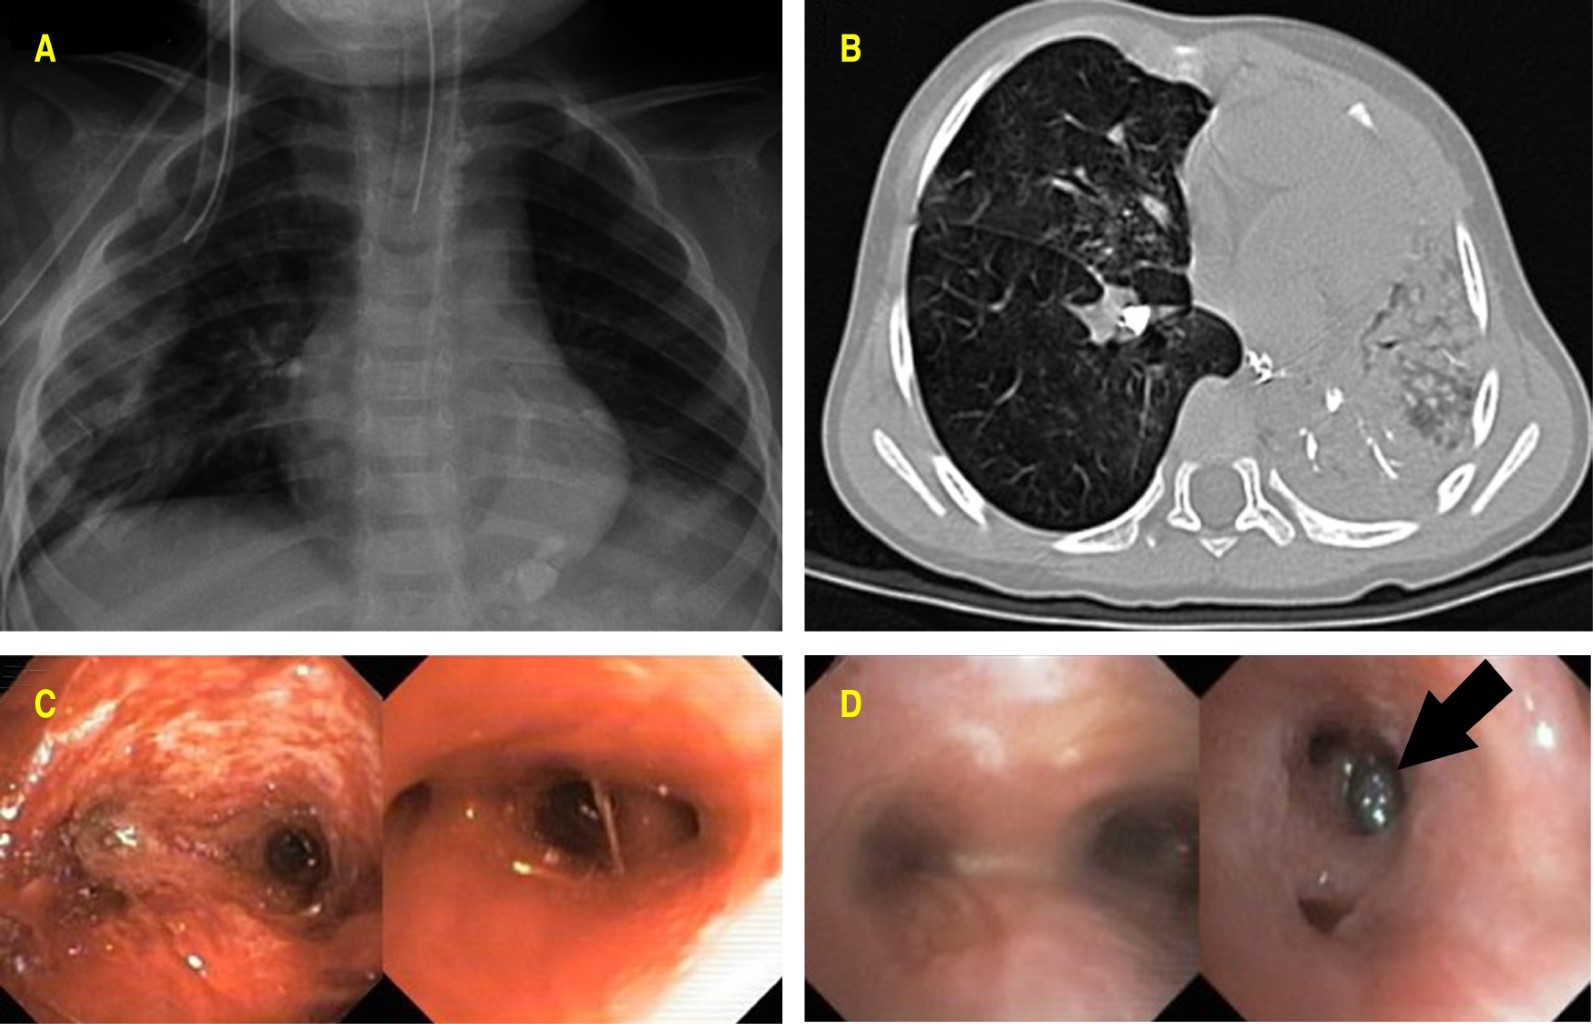

El paciente presentó síndrome de distrés respiratorio agudo pediátrico severo (PARDS) que requirió ventilación convencional durante 20 días, el destete de oxígeno se realizó hasta alcanzar saturaciones normales, fue tratado con doble esquema de antibióticos, esteroide sistémico, micronebulizaciones con esteroide y broncodilatador. Se realizaron tres v ideobroncoscopias flexibles terapéuticas: la primera se efectuó a su ingreso y se observó material inorgánico sólido abundante en la vía aérea, se realizó aspiración y remoción del material referido; en la segunda se observaron datos de traqueoendobronquitis severa, supuración broncopulmonar y zona de isquemia subglótico traqueal, se aspiró material inorgánico sólido; en la tercera broncoscopia se logró la extracción del resto de material sólido (Figura 1).

Los controles radiográficos durante el internamiento mostraron mejoría importante en las zonas de ocupación alveolar, se observaron únicamente algunas bandas de atelectasia. El paciente egresó ventilatoria y neurológicamente estable sin secuelas.

En la radiografía de tórax se observaron zonas radiopacas bilaterales difusas que correspondían a edema alveolar, lo cual a las 24 horas puede ser un predictor clínico posterior al evento de inmersión.12 Los cambios radiológicos más comunes corresponden en distrés respiratorio a zonas de ocupación alveolar y atelectasias bilaterales con sensibilidad del 77% y especificidad del 69% a las ocho horas del evento.12 El tratamiento antibiótico se establece de manera empírica cuando existe la sospecha de aspiración de agua contaminada.13 La tomografía axial computarizada proporciona mayor sensibilidad y especificidad para visualizar el parénquima pulmonar y la vía aérea al tratarse de aspiración de material inorgánico (tierra y piedras). En la sospecha fundada de aspiración de cuerpos extraños se encuentra indicada la instrumentación armada de la vía aérea con broncoscopia flexible o rígida con fines diagnósticos y terapéuticos.14 En la literatura se reporta el caso de casi ahogamiento por aspiración de tierra en una paciente preescolar con realización de broncoscopia seriada con lavado broncoalveolar con mejoría clínica y radiológica.15